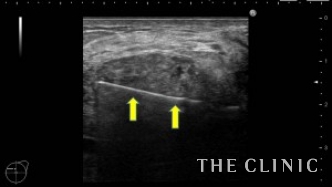

2年前に他院にて片側300㏄ずつの脂肪注入を受けられています。注入後、間もなくしこりを感じるようになり、今回はしこり除去の目的で当院を受診されました。右胸にはオイルシストと充実性のしこり、左胸には47.3㎜の充実性のしこりを認めました。(オイルシストの症例はNo.24でご紹介します)